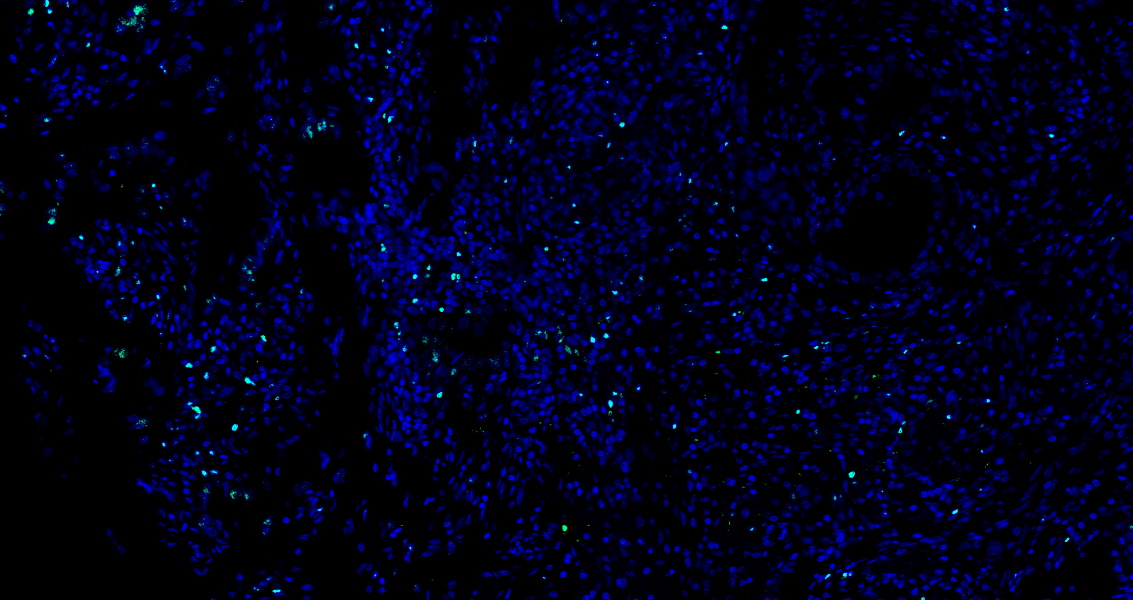

• Tyramide signaling amplification based immunofluorescence was performed on paraffin-embedded human Lung Adenocarcinoma tissue using FOXP3 antibody. Antigen retrieval was performed in EDTA buffer pH 9.0 (95 °C, 20 min) followed by cooling to RT. Then incubated with primary antibody (HY-P80965, 1:100 dilution) at room temperature for 60 minutes and HRP conjugated secondary antibody for 10 minutes. Fluorescence was then developed with TSA520. The tissues were counterstained with DAPI and mounted with Anti-fade mounting medium.